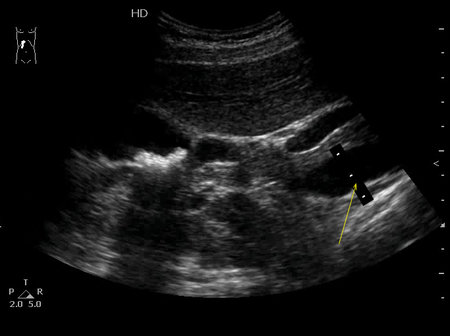

Судя по всему это вы нам сказать должны, но предположу, что где то до 13-15 мм. Изображение

dok69, то что Вы измерили - Это НПВ.

KapustinSV писал(а):dok69, то что Вы измерили - Это НПВ.

Да ..., пардон, промахнулся. Изображение

А чего вы спрашиваете про ВВ?

Если ее здесь не видно.